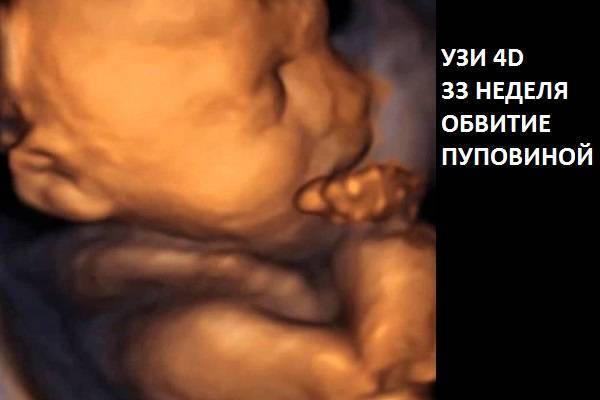

Если характеристики незначительно отклоняются от нормы, то это не критично. Есть несколько показателей, при которых принимается решение об искусственных родах:

обвитие пуповиной;

- расстояние отверстия шейки матки от края плаценты менее 4 см;

- несостоятельность шва на матке после кесарева.